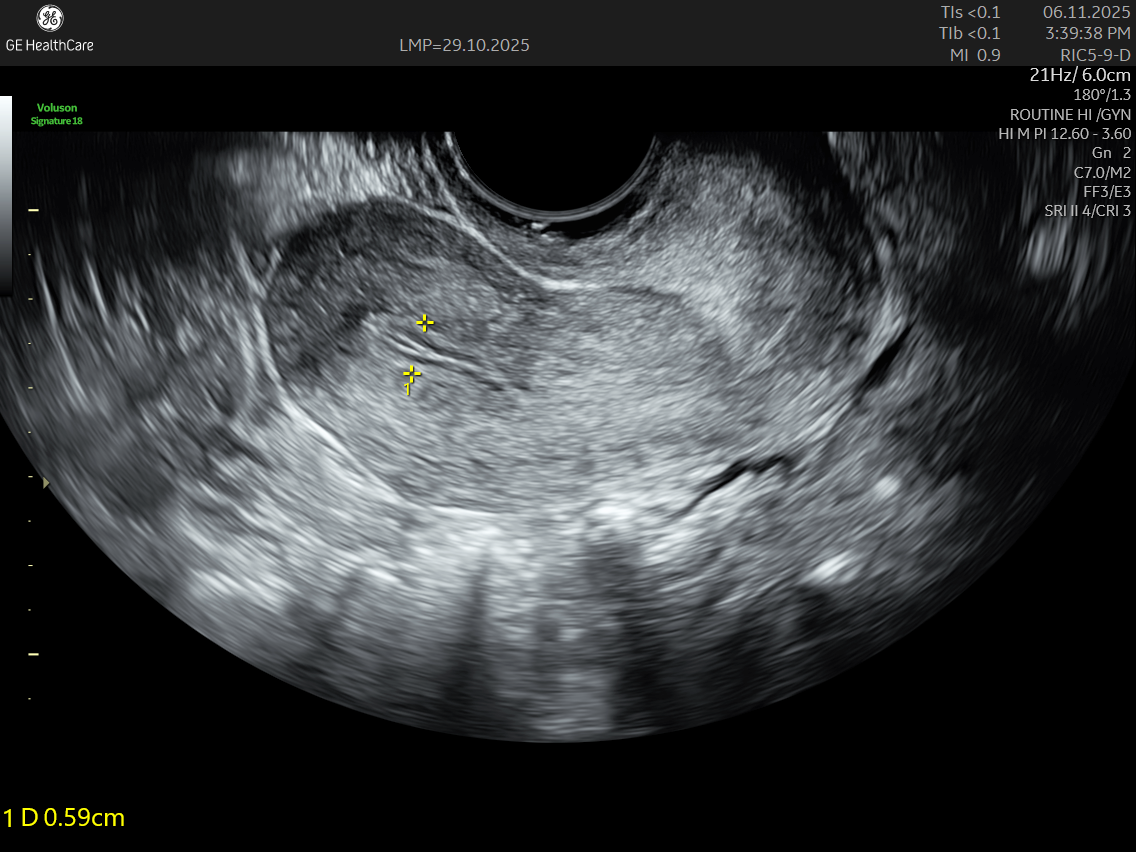

• A transvaginal ultrasound is performed simultaneously to capture detailed images.

IMAGE GALLERY